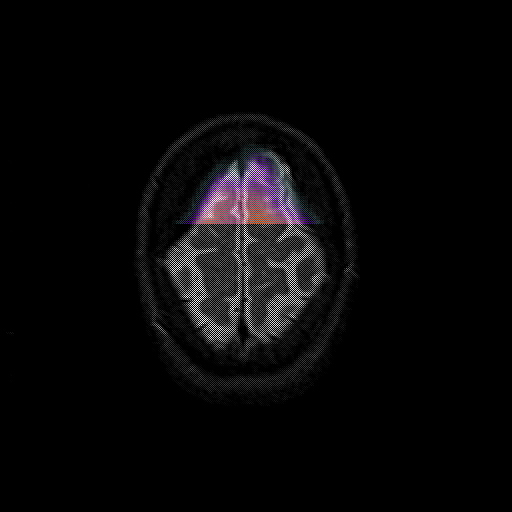

overlay : Slice 47

Slice 47

MRCBFCBF with

T1PDT2T1PDT2